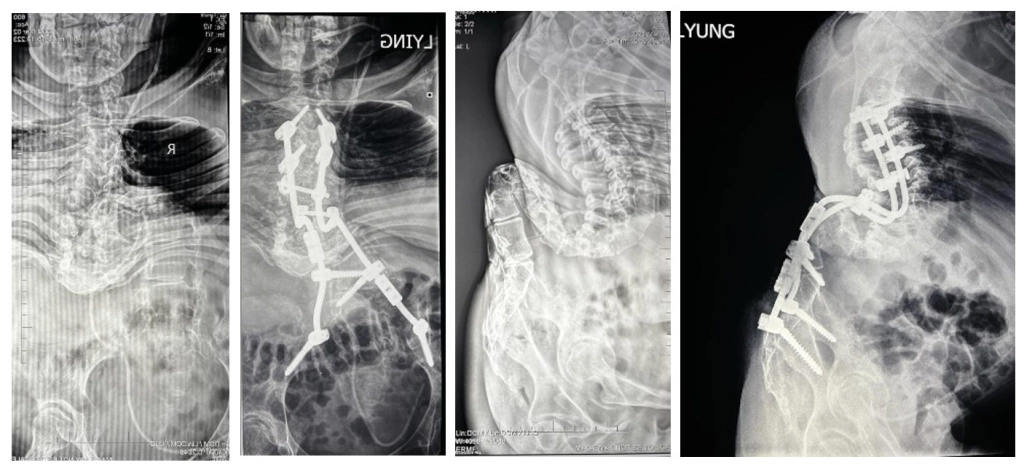

До лечения и после:

• Задний спондилодез

Th1-таз.

• Резекция L1,2,3 позвонков.

• Пластика ТМО.

• Прямая коррекция таза на продольных коннекторах.

Результат лечения